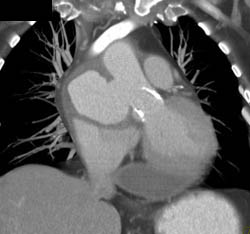

Diagnosis

Large Endoleak